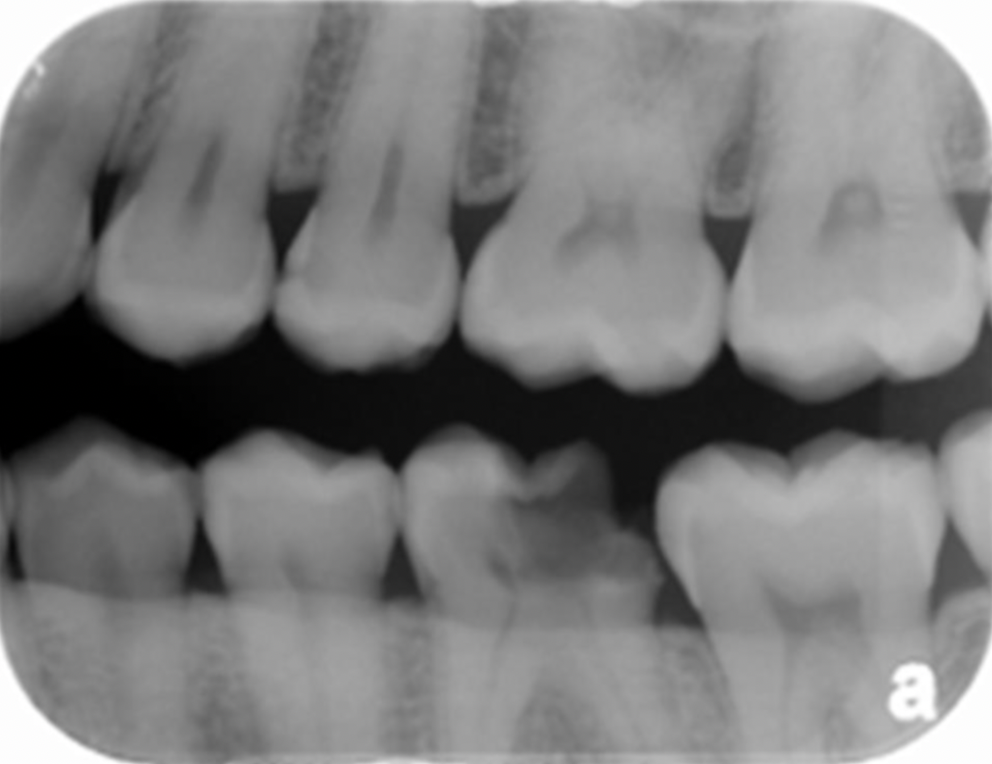

22

Q

Does the following image show correct or incorrect angulation for a bitewing?

A

Incorrect